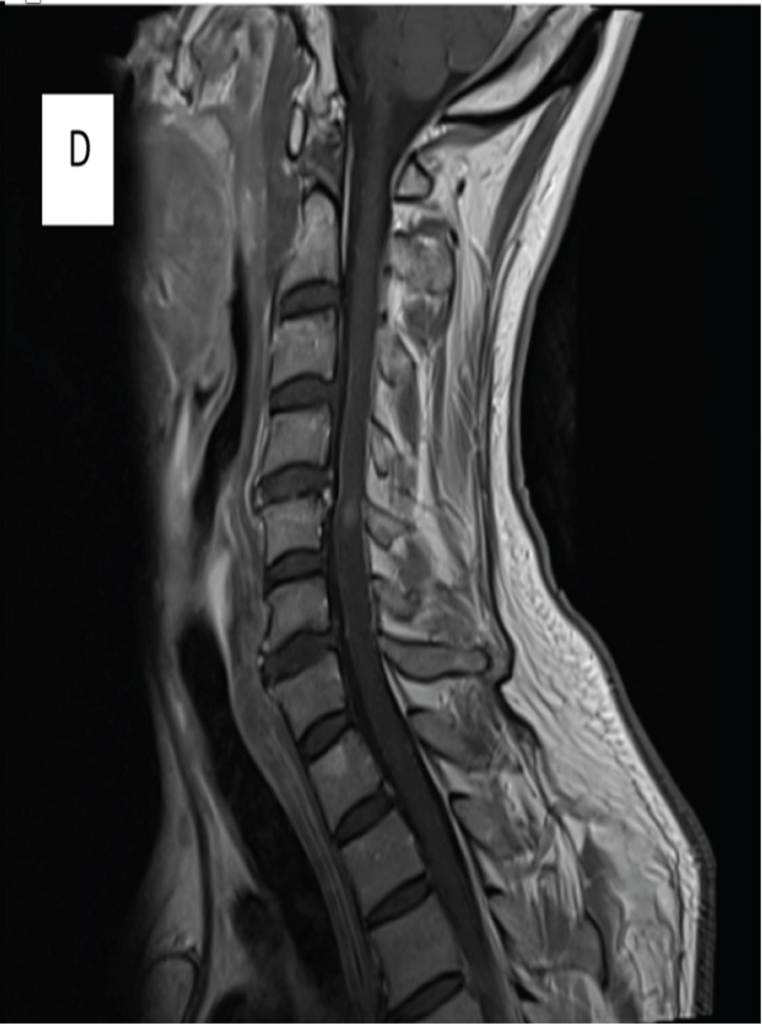

A 64-year-old man developed neck pain after falling off a truck one week ago. T1- and T2-weighted sagittal MR images (1 and 2) are provided. What are the findings? What is your diagnosis?

An extensive low signal intensity epidural abnormality posterior to the vertebral bodies and discs from C2 through C6 (arrows) produces spinal stenosis, most severe at C3, where there is resultant cord compression and faint T2 cord signal hyperintensity. Ossifications are present anterior to the vertebral bodies and discs (arrowheads).

Thick ossification is present posterior to the vertebral bodies and discs corresponding to the MR low signal intensity (arrows). Flowing ossification is present along the anterior vertebral bodies and discs (arrowheads).

ANSWER-

Ossification of the posterior longitudinal ligament (OPLL), continuous type, producing spinal stenosis, cord compression and edema. Diffuse idiopathic skeletal hyperostosis (DISH) is also present.